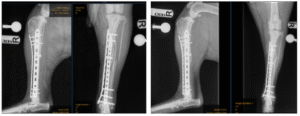

These fissures made surgical repair more complex. The fracture was initially reduced using a screw to realign the bone fragments, before being stabilised with two plates — a large plate placed on the medial (inside) aspect of the tibia and another on the cranial (front) aspect. Due to the fissure lines, no screws could be placed in the central portion of the tibia, as this may have caused further propagation of the fractures.

Immediate post-op & 6 week post-op radiographs

Kes was discharged the following day and has been gradually increasing his exercise over the past six weeks. He recently returned for his post-operative radiographs, and we’re very pleased to report that the fracture is healing well. The plan now is to continue a gradual increase in exercise over the next five weeks, with the goal of returning to normal activity.